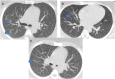

COVID-19 has been associated with central nervous system manifestations; however, cerebral venous thrombosis is rarely reported. A 34-year-old woman was admitted to the hospital with headache and recurrent seizures; she was recently discharged after COVID-19 pneumonia. Cranial magnetic resonance imaging and magnetic resonance venography showed cortical vein thrombosis in the right frontal lobe. SARS-CoV-2 RNA was detected in cerebrospinal fluid analysis. The patient was anticoagulated and put on antiepileptics. The most probable mechanism underlying the venous thrombosis is COVID-19-associated hypercoagulability. However, the relation between the viral RNA in cerebrospinal fluid analysis and the thrombosis is controversial.